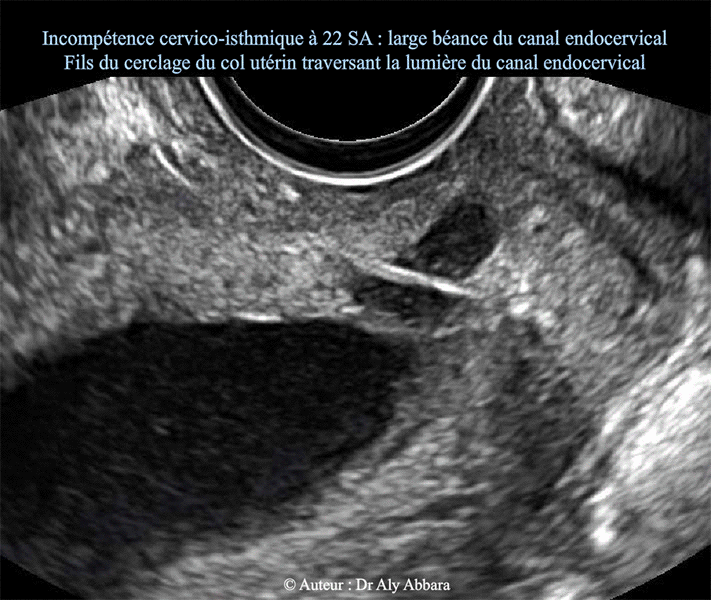

• Incompétence cervico-isthmique : à 22 SA

• Un mois après la réalisation à froid d'un cerclage prophylactique du col utérin pour antécédents de multiples avortements tardifs liés à une incompétence congénitale cervico-isthmique.

• On observe sur ces images, la large béance cervico-isthmique avec un canal endocervical perméable sur 90 % de son trajet (longueur utile restant fermée = 4 mm).

On remarque aussi que le fil du cerclage du col utérin (réalisé par faufilage sous muqueux) traverse le canal endocervical par section (comme un fil à couper le beurre) des tissus constituant les parois de col utérin ; cela est dû au tiraillement et la pression importants exercés par la poche des eaux sur le fil du cerclage ; en effet, l'incompétence cervico-isthmique permet facilement l'intrusion de la poche amniotique dans le canal endocervical, puis cette poche amniotique je le rôle de dilatateur-effaceur du col utérin dans le sens "orifice interne > orifice externe" du canal cervical.

• Chez cette patiente, pas de contractions utérines ressenties malgré les modifications importantes du col utérin constatées à l'échographie.